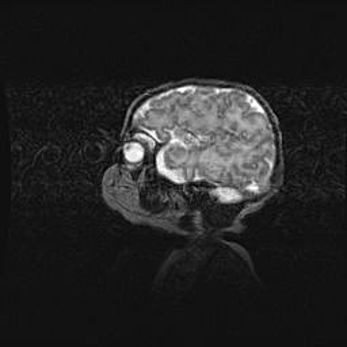

Мальформация Денди-Уокера. Киста задней черепной ямки.

Агенезия мозолистого тела.

Возраст: 2,5 месяца

Вес: 2420 г

Пол: женский

Окружность головы: 37 см

Срок гестации: 32 недели

Мальформация Денди—Уокера — редкий вид патологии ЦНС, представляющий собой врожденный порок развития каудального отдела ствола и червя мозжечка, ведущий к неполному раскрытию срединной (Мажанди) и латеральных (Лушка) апертур IV желудочка мозга. Для этогно синдрома характерна триада симптомов: гипотрофия червя мозжечка и/или полушарий мозжечка, кисты задней черепной ямки, гидроцефалия различной степени. В 70% случаев порок сочетается и с другими аномалиями головного мозга, в частности с агенезией мозолистого тела.